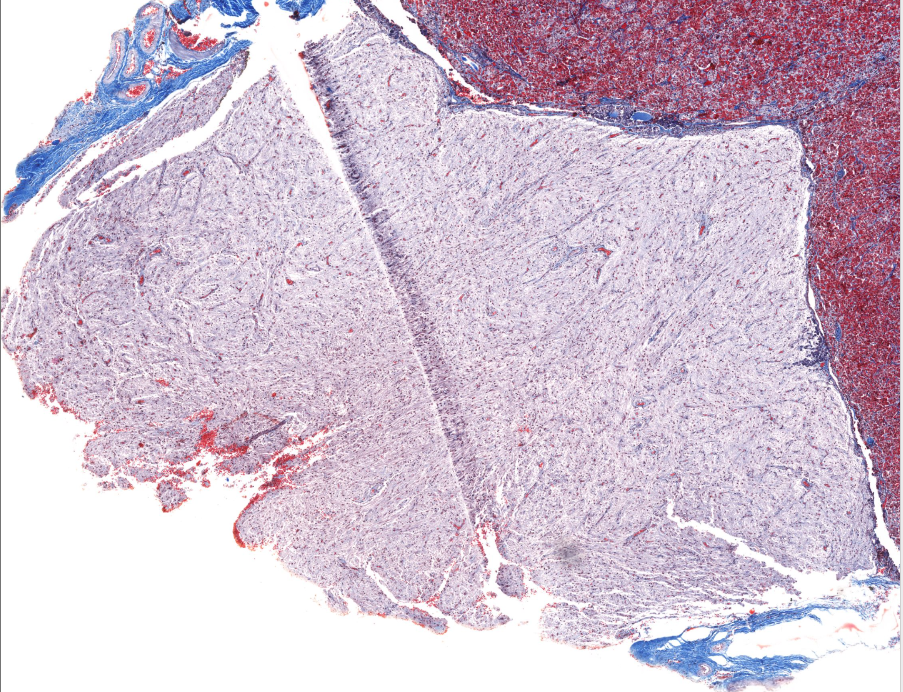

prostate gland

secretes prostatic fluid???

identifiable by the dark purple structures